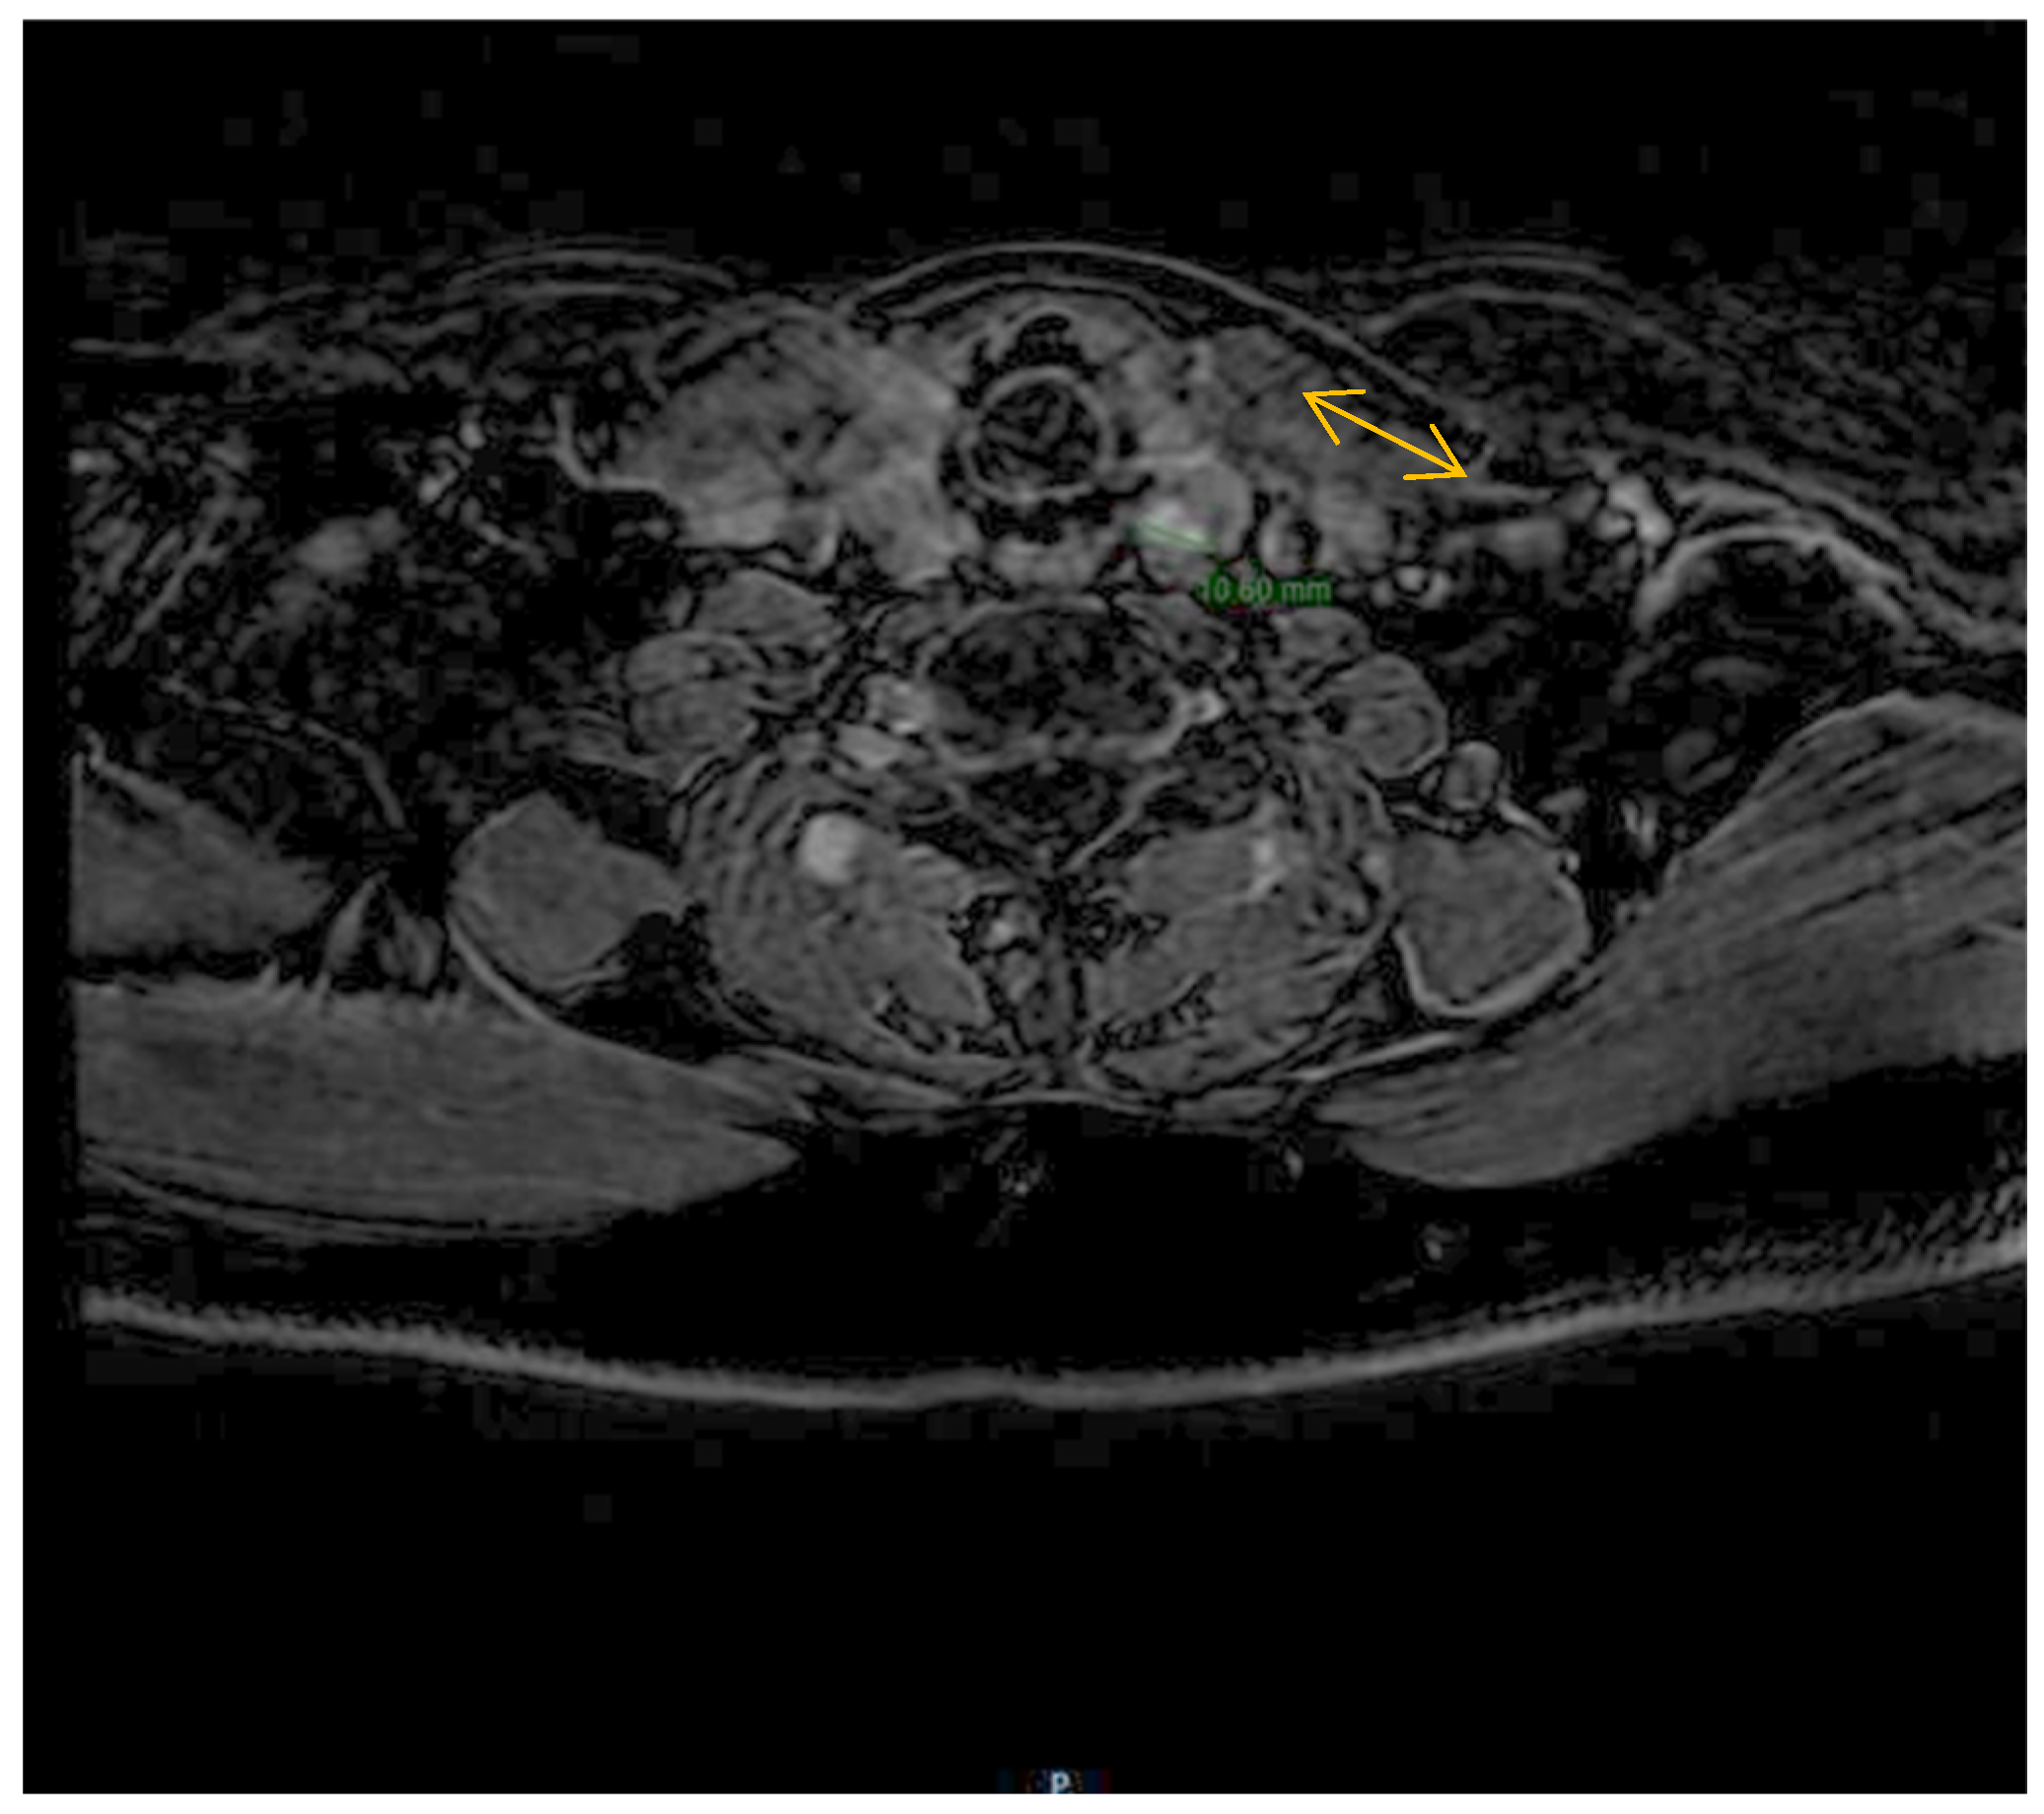

Despite the initial successful surgical intervention, the patient experienced a relapse of the disease after two months. Laboratory tests, including serum calcium, phosphate, and PTH measurements, indicated a relapse of the patient’s condition. Neck magnetic resonance imaging (MRI) was performed, which revealed the presence of a new nodular mass adjacent to the left thyroid lobe, located at the base of the cricoid cartilage. The mass measured 1.1 cm and exhibited imaging characteristics indicative of parathyroid carcinoma, including T2 isosignal, gadolinium enhancement, and hypersignal on diffusion-weighted imaging (DWI) without a corresponding signal on apparent diffusion coefficient (ADC) imaging. These imaging findings confirmed a possible relapse of the patient’s condition (Figure 3).

Figure 3.

Neck MRI shows a new nodular mass of 11 mm adjacent to the left thyroid lobe at the base of the cricoid cartilage.